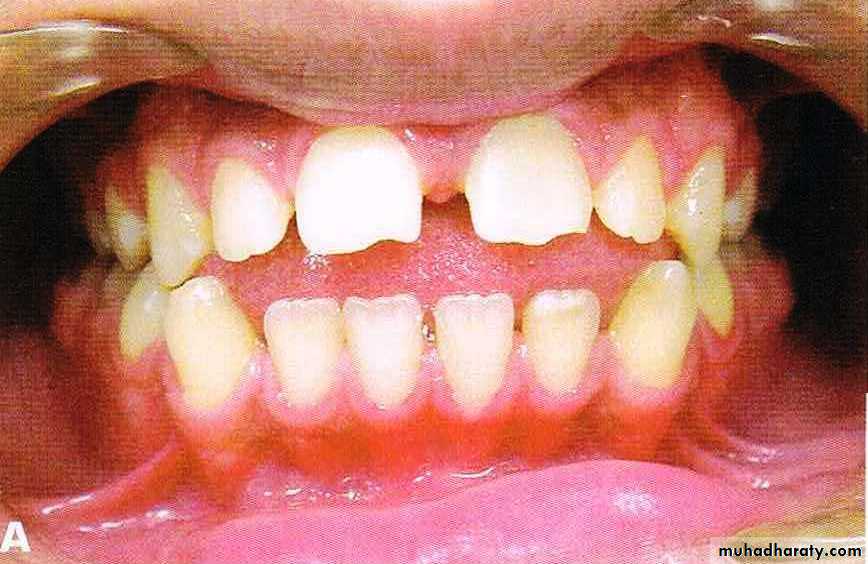

Bimaxillary proclination: the teeth are proclined on normal bases

Bimaxillary protrusion or bialveolar protrusion refers to a protrusive dentoalveolar position of maxillary and mandibular dental arches that produces aconvex facial profile .Bimaxillary prognathism: the jaws/basal bones are forward relative to the cranial base

Features

• Soft tissue• Convex facial form.

• Reduced lip length.

• Lips incompetency.

• Low lower lip line and high upper lip line

• prominent lips.

• Receded chin.

• Dental

• Dental bimaxillary proclination• Larger dental arch length with resultant spacing and diastema

• Normal or increased OJ

• Variable molar relationship but usually normal.

• Large teeth compared to normal population

• May have other superimposed malocclusion